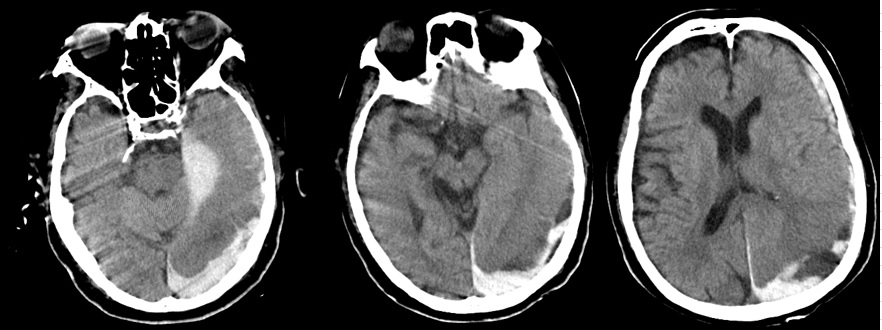

- 9月12日:急性硬膜下血腫

死亡した日の頭部CTで重度の急性硬膜下血腫。医師によれば「その原因はDICによる出血傾向」(頭部打撲の説明なし)。

証拠:頭部CT・急性硬膜下血腫

- 9月12日:出血傾向はごく軽度

PT-INR 1.3, APTT 35 sec, 血小板3.6万/μl, Hb 8.2 g/dl:出血傾向はごく軽度で硬膜下血腫の自然発生は否定的。この時、父は意識がなく自ら動くことはできない状態であったため、頭部を殴打された可能性しか残らない。

証拠:血液検査データ(9月12日)

状態が悪化した9月12日に頭部・胸腹部CTが撮影された。医師説明およびカルテ記載には、そのCTの目的として 「貧血が進行したため出血源精査目的」とあるが、頭部への出血で貧血が進行することは通常考えられず、 出血源精査目的であれば、胸腹部CTで十分のはずである。 このCTの目的は、医学的には死後AI(Autopsy Imaging)に他ならない。 つまり、死因の特定である。

この時、撮影された頭部CTで急性硬膜下血腫が認められた。これが父の直接の死因となった。 医師からもその説明があったが、 直接の原因と推定される「頭部打撲」には一切言及がなく(録音記録あり)、 DIC(播種性血管内凝固)に伴う出血傾向による自然出血とのことだった。 しかしほぼ同時に行われた血液検査では、「PT-INR 1.3, APTT 35 sec, 血小板3.6万/μl」と 出血傾向はごく軽度であり、自然発生的に頭蓋内に出血を起こす可能性は皆無と言ってよい。

このことから、直接の死因である急性硬膜下血腫の原因は頭部打撲と確定できる。 この時点で父の意識はなく、自ら動くことは全くできない状態であることから、 頭部打撲は外力によって起こった、と推定される。つまり変死である。

硬膜下血腫がなかったとしても父は回復不能であり、早晩、死に至る病状ではあった。 医療事故を闇に葬るための故意の放置、そして死期を早めるための頭部殴打、 というのが、医療記録と経過から必然的に導き出された結論である。